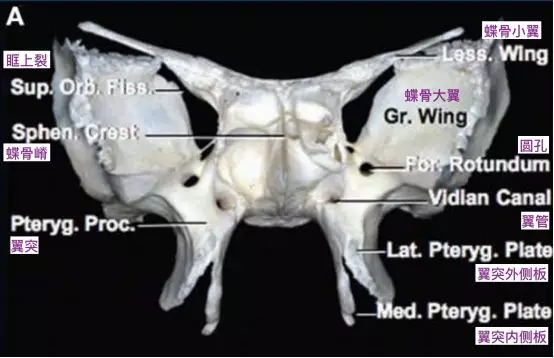

圆孔连接中颅窝底和翼腭窝,而翼管连接翼腭窝和破裂孔。圆孔位于翼管的上、外侧。

蝶骨,前面观(Osawa 2009)。翼管位于蝶骨翼突和蝶骨体融合的交界处。翼管前方的开口位于翼突上表面上内侧部分,位于蝶窦底水平,圆孔的下内侧。

翼腭窝前内侧观示意图,注意圆孔和翼管的位置(Standring, 2016)。